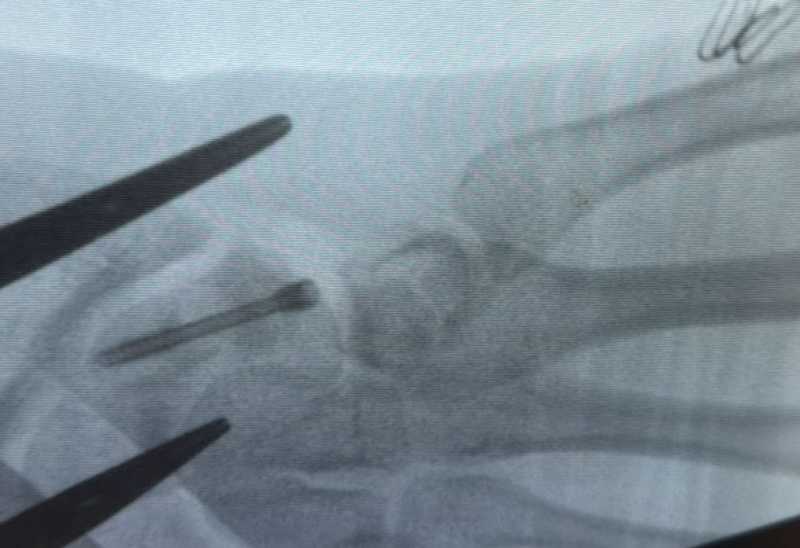

'La aproape un an de la traumatism, persistența durerii și limitarea funcției mâinii au impus trimiterea pacientului dintr-o altă unitate spitalicească pentru tratament chirurgical de specialitate. În urma investigațiilor imagistice (RMN, radiografii) și a consulturilor de specialitate, medicul curant, Dr. Alexandru Pîrvan, a diagnosticat pacientul cu fractură de os scafoid drept, cu deficit de consolidare, evoluată către pseudoartroză, asociată cu ruptură parțială a ligamentului scafo-lunar', a informat purtătoarea de cuvânt a spitalului, Lisa Crăiuț.

Pacientul a fost programat pentru intervenție chirurgicală, care a avut loc în ultimele zile ale anului 2025. Operația a constat într-o incizie de aproximativ 5 centimetri, cu curățarea focarului de pseudoartroză la nivelul osului scafoid și stabilizarea fracturii prin montarea unui șurub Herbert, utilizând o tehnică chirurgicală specială. Acest tip de șurub se remarcă prin faptul că nu necesită extragere ulterioară, fiind conceput fără vârf, el rămâne in corp și după ce osul s-a vindecat.